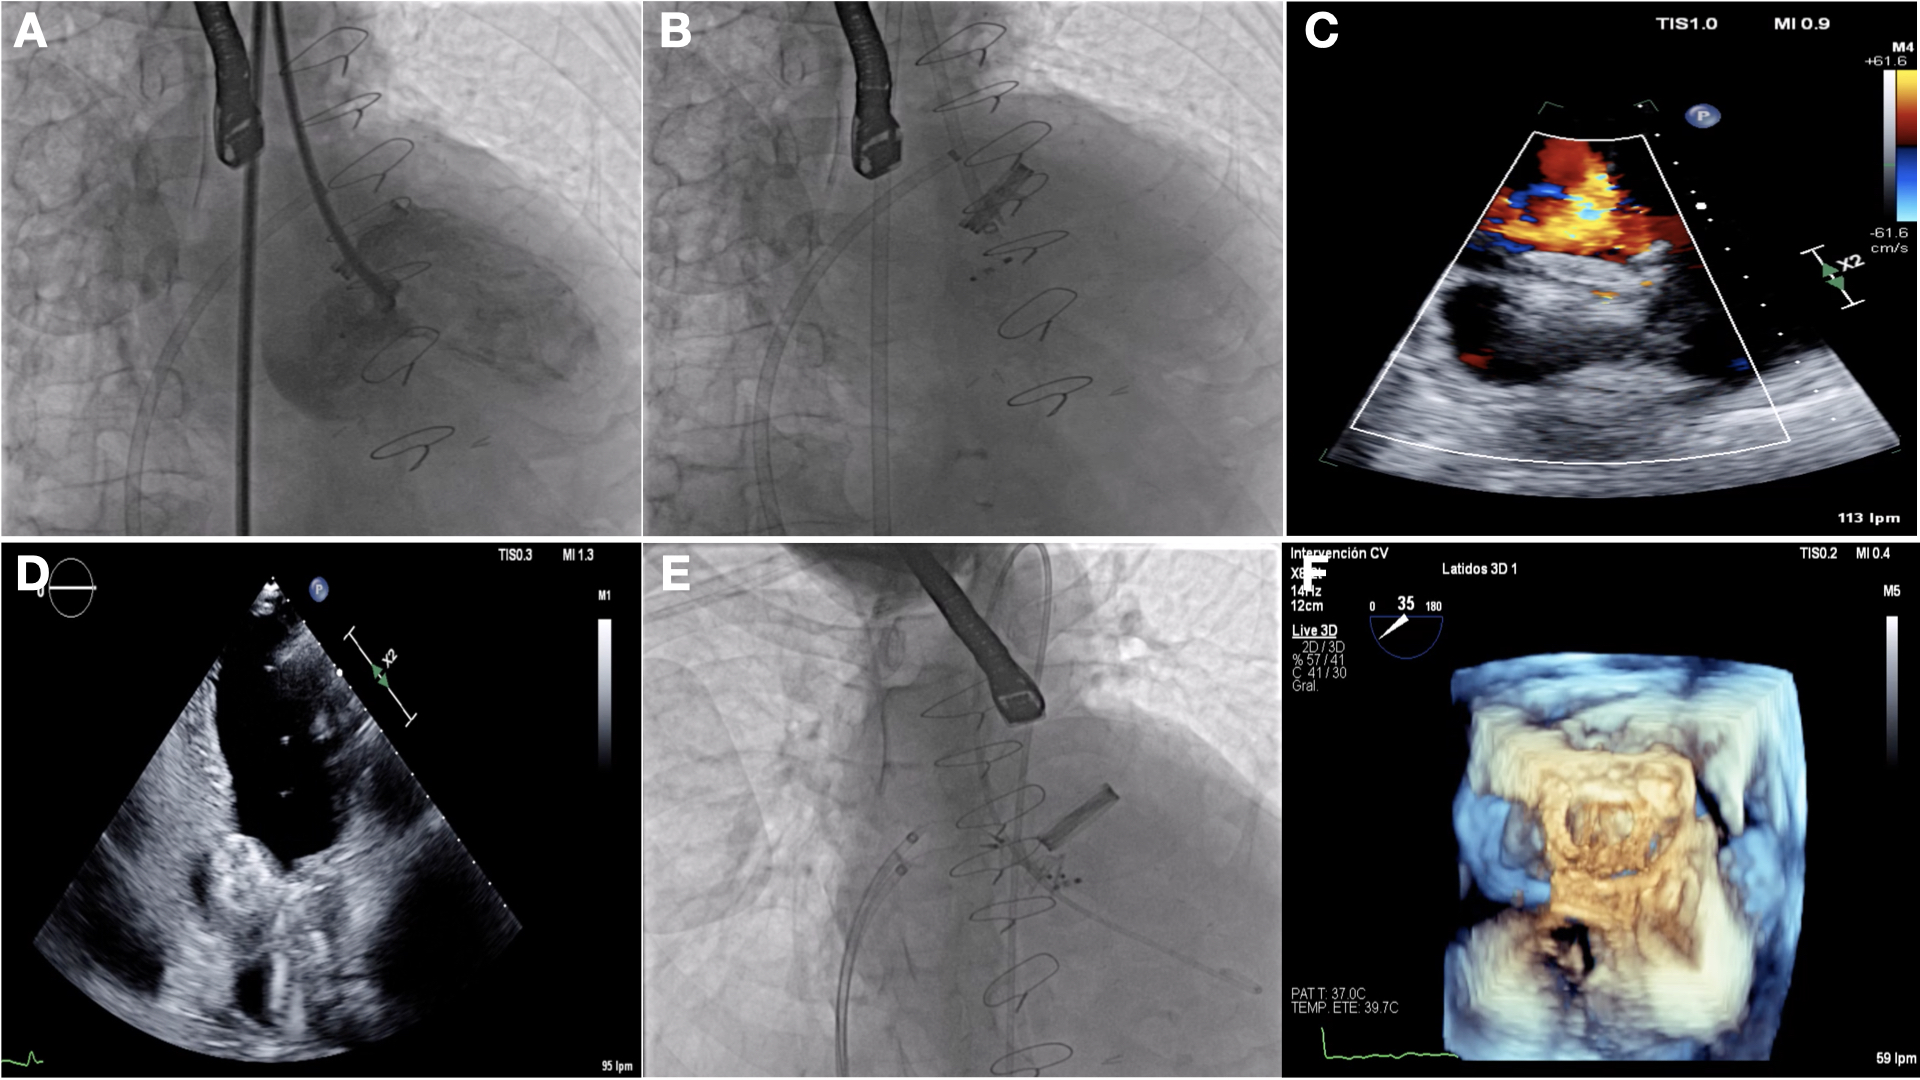

The procedure was performed under general anesthesia and TEE monitoring with femoral venous and arterial access. First, an antegrade approach was attempted by transeptal puncture using an Agilis 8.5-French (Fr) steerable catheter (Abbott), but due to angulation it was not possible to reach the pseudoaneurysm. Thus, we decided to switch to retrograde access, by which it was sucessfully reached (Video 1). Next, we implanted a 25-mm Amplatzer Cribriform Multi-Fenestrated Septal Occluder (Abbott) with a 10-Fr delivery system tight to the narrowest area, which remained stable after safety maneuvers (Figure 2A-D). This device is flexible, with less radial force than others, which allows it to adapt to frail structures.1,2 Afterward, by antegrade access, 2 parallel 7-Fr sheaths were advanced through the paravalvular leak with simultaneous deployment of two 10 x 5-mm Amplatzer Vascular Plug IIIs (Abbott) (Figure 2E and F).